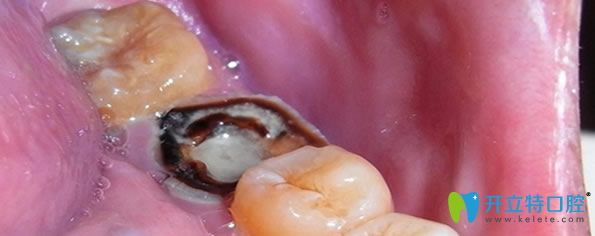

二、牙髓炎不治療會(huì)怎么樣?

牙髓炎是一種嚴(yán)重的制病因素,一旦發(fā)炎不能好轉(zhuǎn),不是吃了消炎藥就可以恢復(fù),牙髓炎持續(xù)惡化,繼續(xù)發(fā)展就會(huì)造成牙髓死亡。牙齒沒有得到及時(shí)的診治,久而久之,牙齦就會(huì)萎縮,牙齒就會(huì)變得稀疏松動(dòng),導(dǎo)致牙齒脫落。

急性牙髓炎不治療的后果